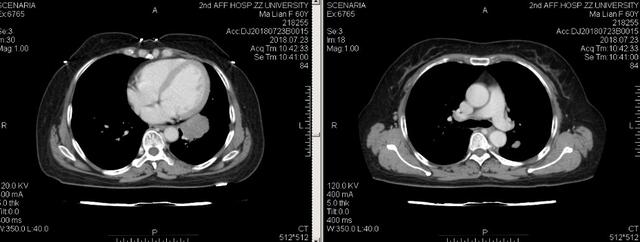

-患者:女,50岁

-主诉:发现双肺结节1年半,左肺上叶结节术后3月余

-病史:患者于2018年3月当地医院行胸部CT发现双肺结节,2018年6月于兰大二院行PET-CT示:右肺下叶内基底段磨玻璃结节,轻度代谢,余双肺多发大小不等磨玻璃结节及部分微小实性结节,无明显代谢

患者定期复查,于2019年4月行胸CT检查提示双肺多发结节,左肺上叶结节较前实性成分增加2019年5月7日全麻下行“荧光胸腔镜下左肺上叶楔形切除术”术后病理提示:原位腺癌,癌组织为两灶。EGFR基因检测结果:21外显子-L858R突变辅助检查入院胸部CT检查提示:双肺多发磨玻璃样结节

2019-08-31 全麻下行“荧光胸腔镜下右肺上叶及右肺下叶楔形切除术”

术后病理提示:见术后病理报告。EGFR基因检测结果:19外显子-Del突变

讨论点

1 该患者病理分期:Ⅰ期?Ⅳ期?

2 该患者术后长期处理策略:定期随访复查内科干预?

点评

1 该患者多点原发的可能性比较大,发病机制以驱动基因为主,因此分期应当为Ⅰ期,后续治疗建议以靶向治疗维持。

2 多于多点原发病灶建议靶向治疗维持,以预防未来患者其他部位发生肿瘤。

3 该患者是多点原发还是转移需要更明确的证据判断,可以注意患者病情发展的快慢。

4 肺部结节超过8mm是干预的指征,目前临床对肺结节的干预比较积极,早期肺癌的发现也越来越多,经检查无其他地方转移的情况下,首先考虑是早期肺癌。如果患者结节增大很慢,随访400天没有改变,就不需要过早干预。该患者不同部位的结节可能驱动基因也不同,还存在其他类型的突变,给TKI治疗带来困难,建议不需要太主动干预,可以3个月后检查,如果没有增大,可以延长随访时间至6个月。